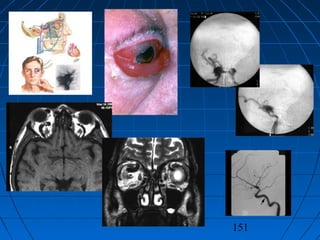

KAROTİKO-KAVERNÖZ FİSTÜLKAROTİKO-KAVERNÖZ FİSTÜL

TANIMTANIM

 A. carotis internaA. carotis interna’nın kavernöz’nın kavernöz

sinüs içinden geçerken verdiğisinüs içinden geçerken verdiği

meningo-hipofizeal dallarınmeningo-hipofizeal dalların

hasarıhasarı ile karotis arteri veile karotis arteri ve

kavernöz sinüs arasında oluşankavernöz sinüs arasında oluşan

arterio-venöz bir fistülarterio-venöz bir fistül

 En önemli nedeniEn önemli nedeni travmatravma,,

spontan da oluşabilirspontan da oluşabilir

 ÇoğunluklaÇoğunlukla ön çukur fraktürleriön çukur fraktürleri

sonucunda görülürsonucunda görülür

KLİNİKKLİNİK

 ÇoğunluklaÇoğunlukla ünilateralünilateral

 Travmayı izleyen günlerdeTravmayı izleyen günlerde

gözdegözde pulsatil egzoftalmi,pulsatil egzoftalmi,

kemozis ve üfürümkemozis ve üfürüm

 Vizyon azalmasıVizyon azalması

 Karotis akımı durdurulursaKarotis akımı durdurulursa

üfürüm kaybolurüfürüm kaybolur

 Spontan olarak iyileşmeSpontan olarak iyileşme

TANITANI

 KlinikKlinik

 ÜfürümÜfürüm

dinlenmesidinlenmesi

 BTBT

 MRG - MRAMRG - MRA

 DSADSA

151